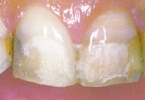

■CASE-1.(前装冠)

Sinfonyは前装冠であっても硬質レジン特有のツヤの消失が少なく、透明感が持続します。

[術前] [装着]